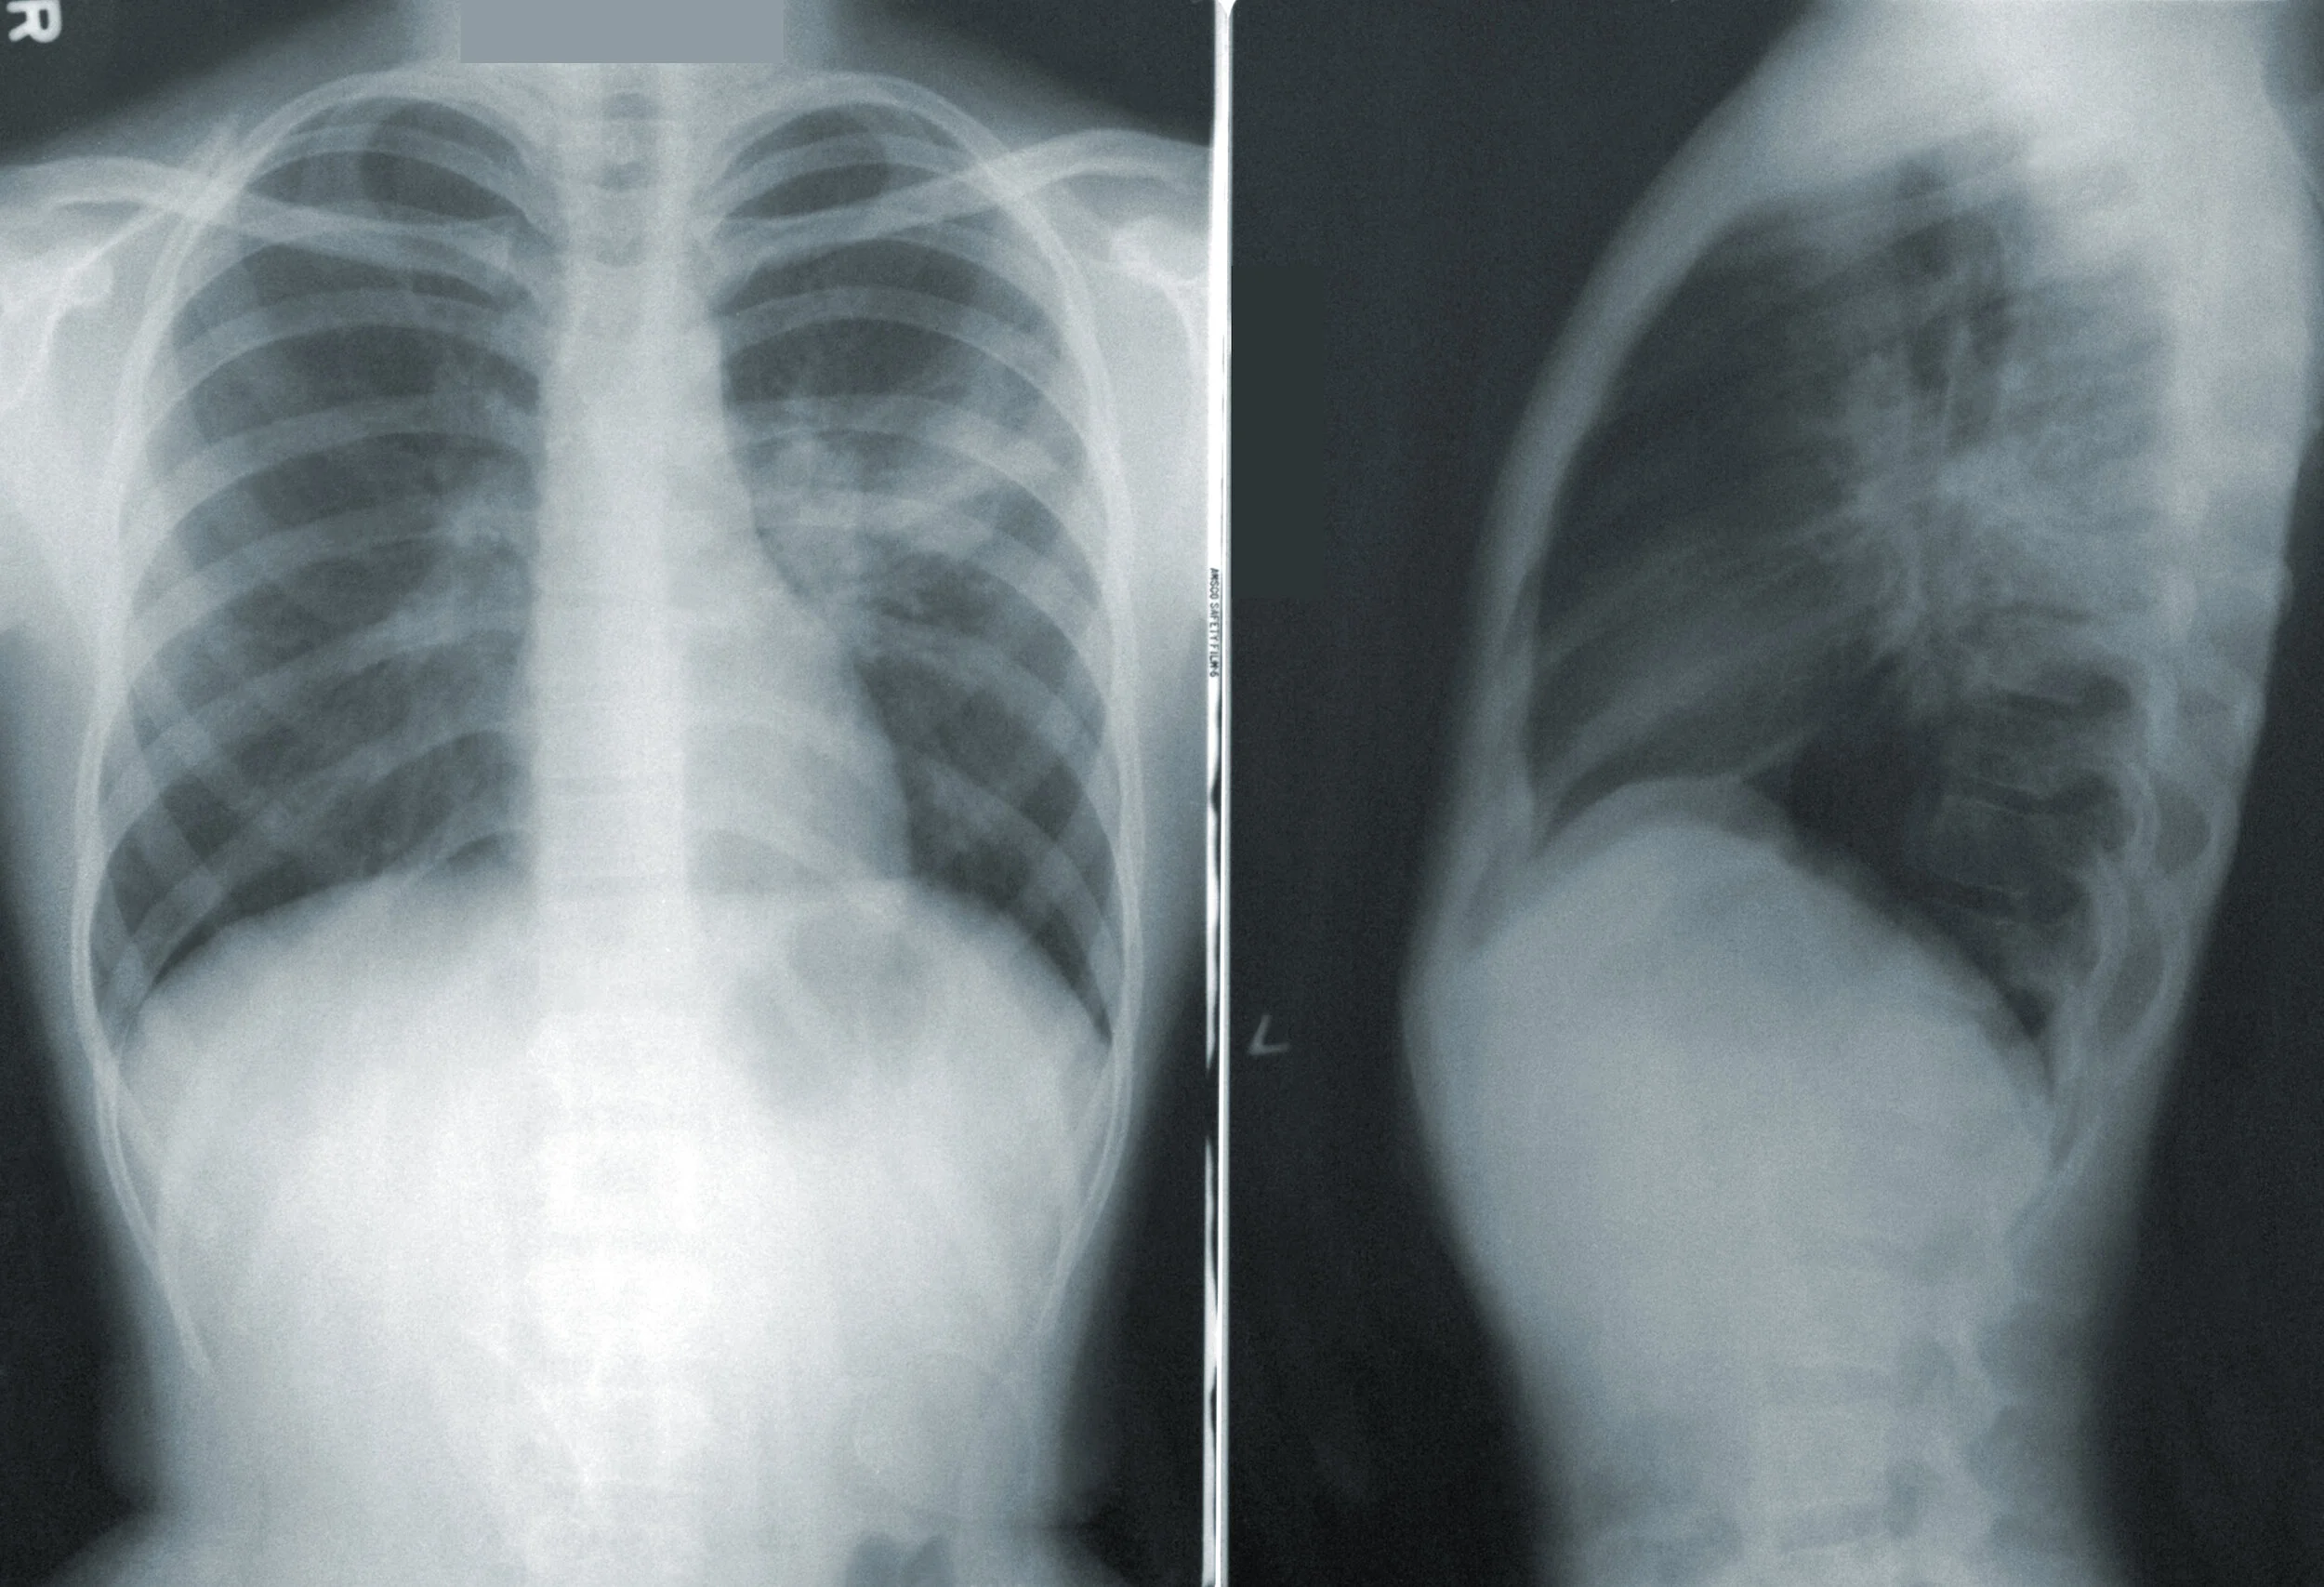

Imaging in lung cancer is far from perfect. A chest x-ray cannot distinguish lung cancer from a…